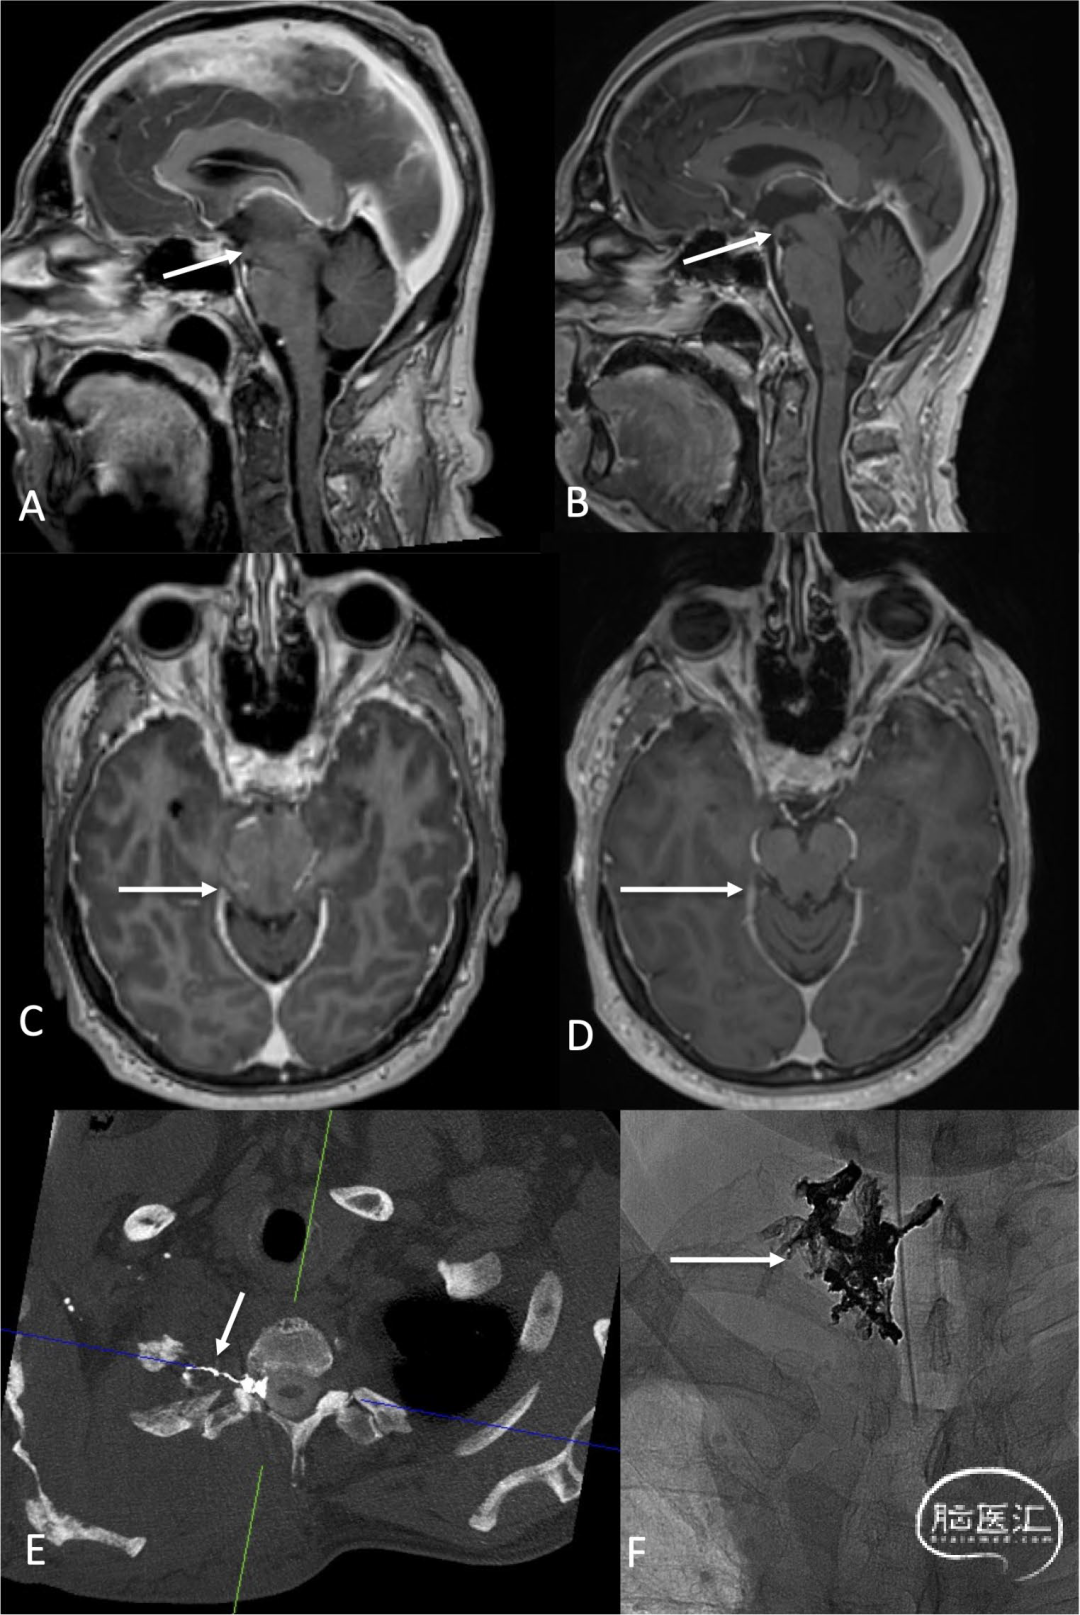

图2.男性,64岁。表现为无自控能力、头晕和语言障碍,无法再从事教师工作。MRI显示中脑严重下垂,乳头-桥脑(mamillo-pontine)距离很短(A:箭头),中脑延长(B:箭头)。动态CT脊髓造影显示右侧T2神经根处存在脑脊液静脉瘘(C:箭头)。经静脉栓塞后(F:箭头为Onyx铸型),MRI变化逐渐消退(D、E:箭头),患者报告明显改善: